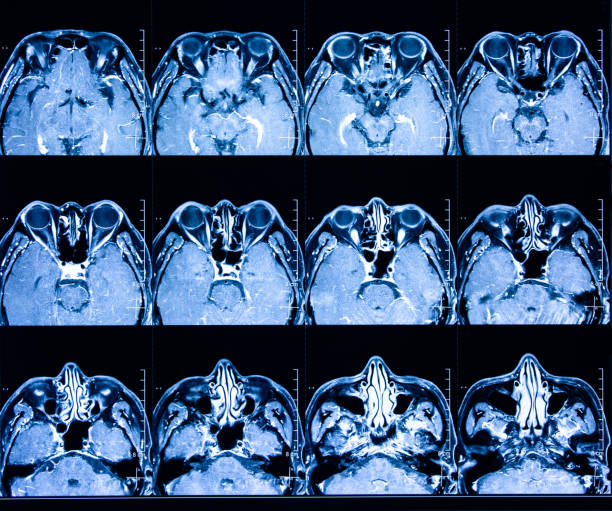

為了描述目的,患者按入組順序被賦予編號,并被連續(xù)分配到三組中的一組,每組三名。根據(jù)模型2分割,ICH體積范圍為0.1至54.9mL(平均ICH體積為23.5mL)。5名ICH患者受累于局限性腦葉,其余患者受累于基底神經(jīng)節(jié)或外囊深處。3名患者的ICH位于丘腦(圖1),1名患者的血腫位于多個(gè)腦結(jié)構(gòu)(即尾狀核、殼核和蒼白球)。平均而言,MSCs是在ICH后3天注射的。